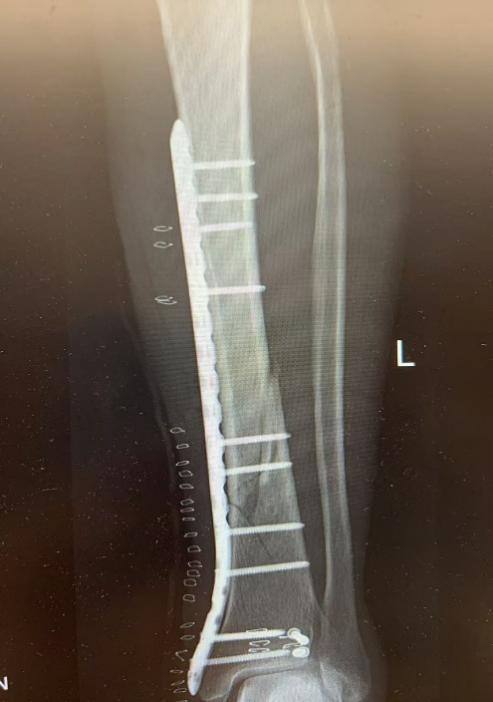

10月3日,60岁的陆女士(化名)滑倒后右手撑地,16:30入院就诊,顾晓娟医师团队诊断为:右尺桡骨骨折,充分评估后,22:00开始手术,1小时后返回病房。